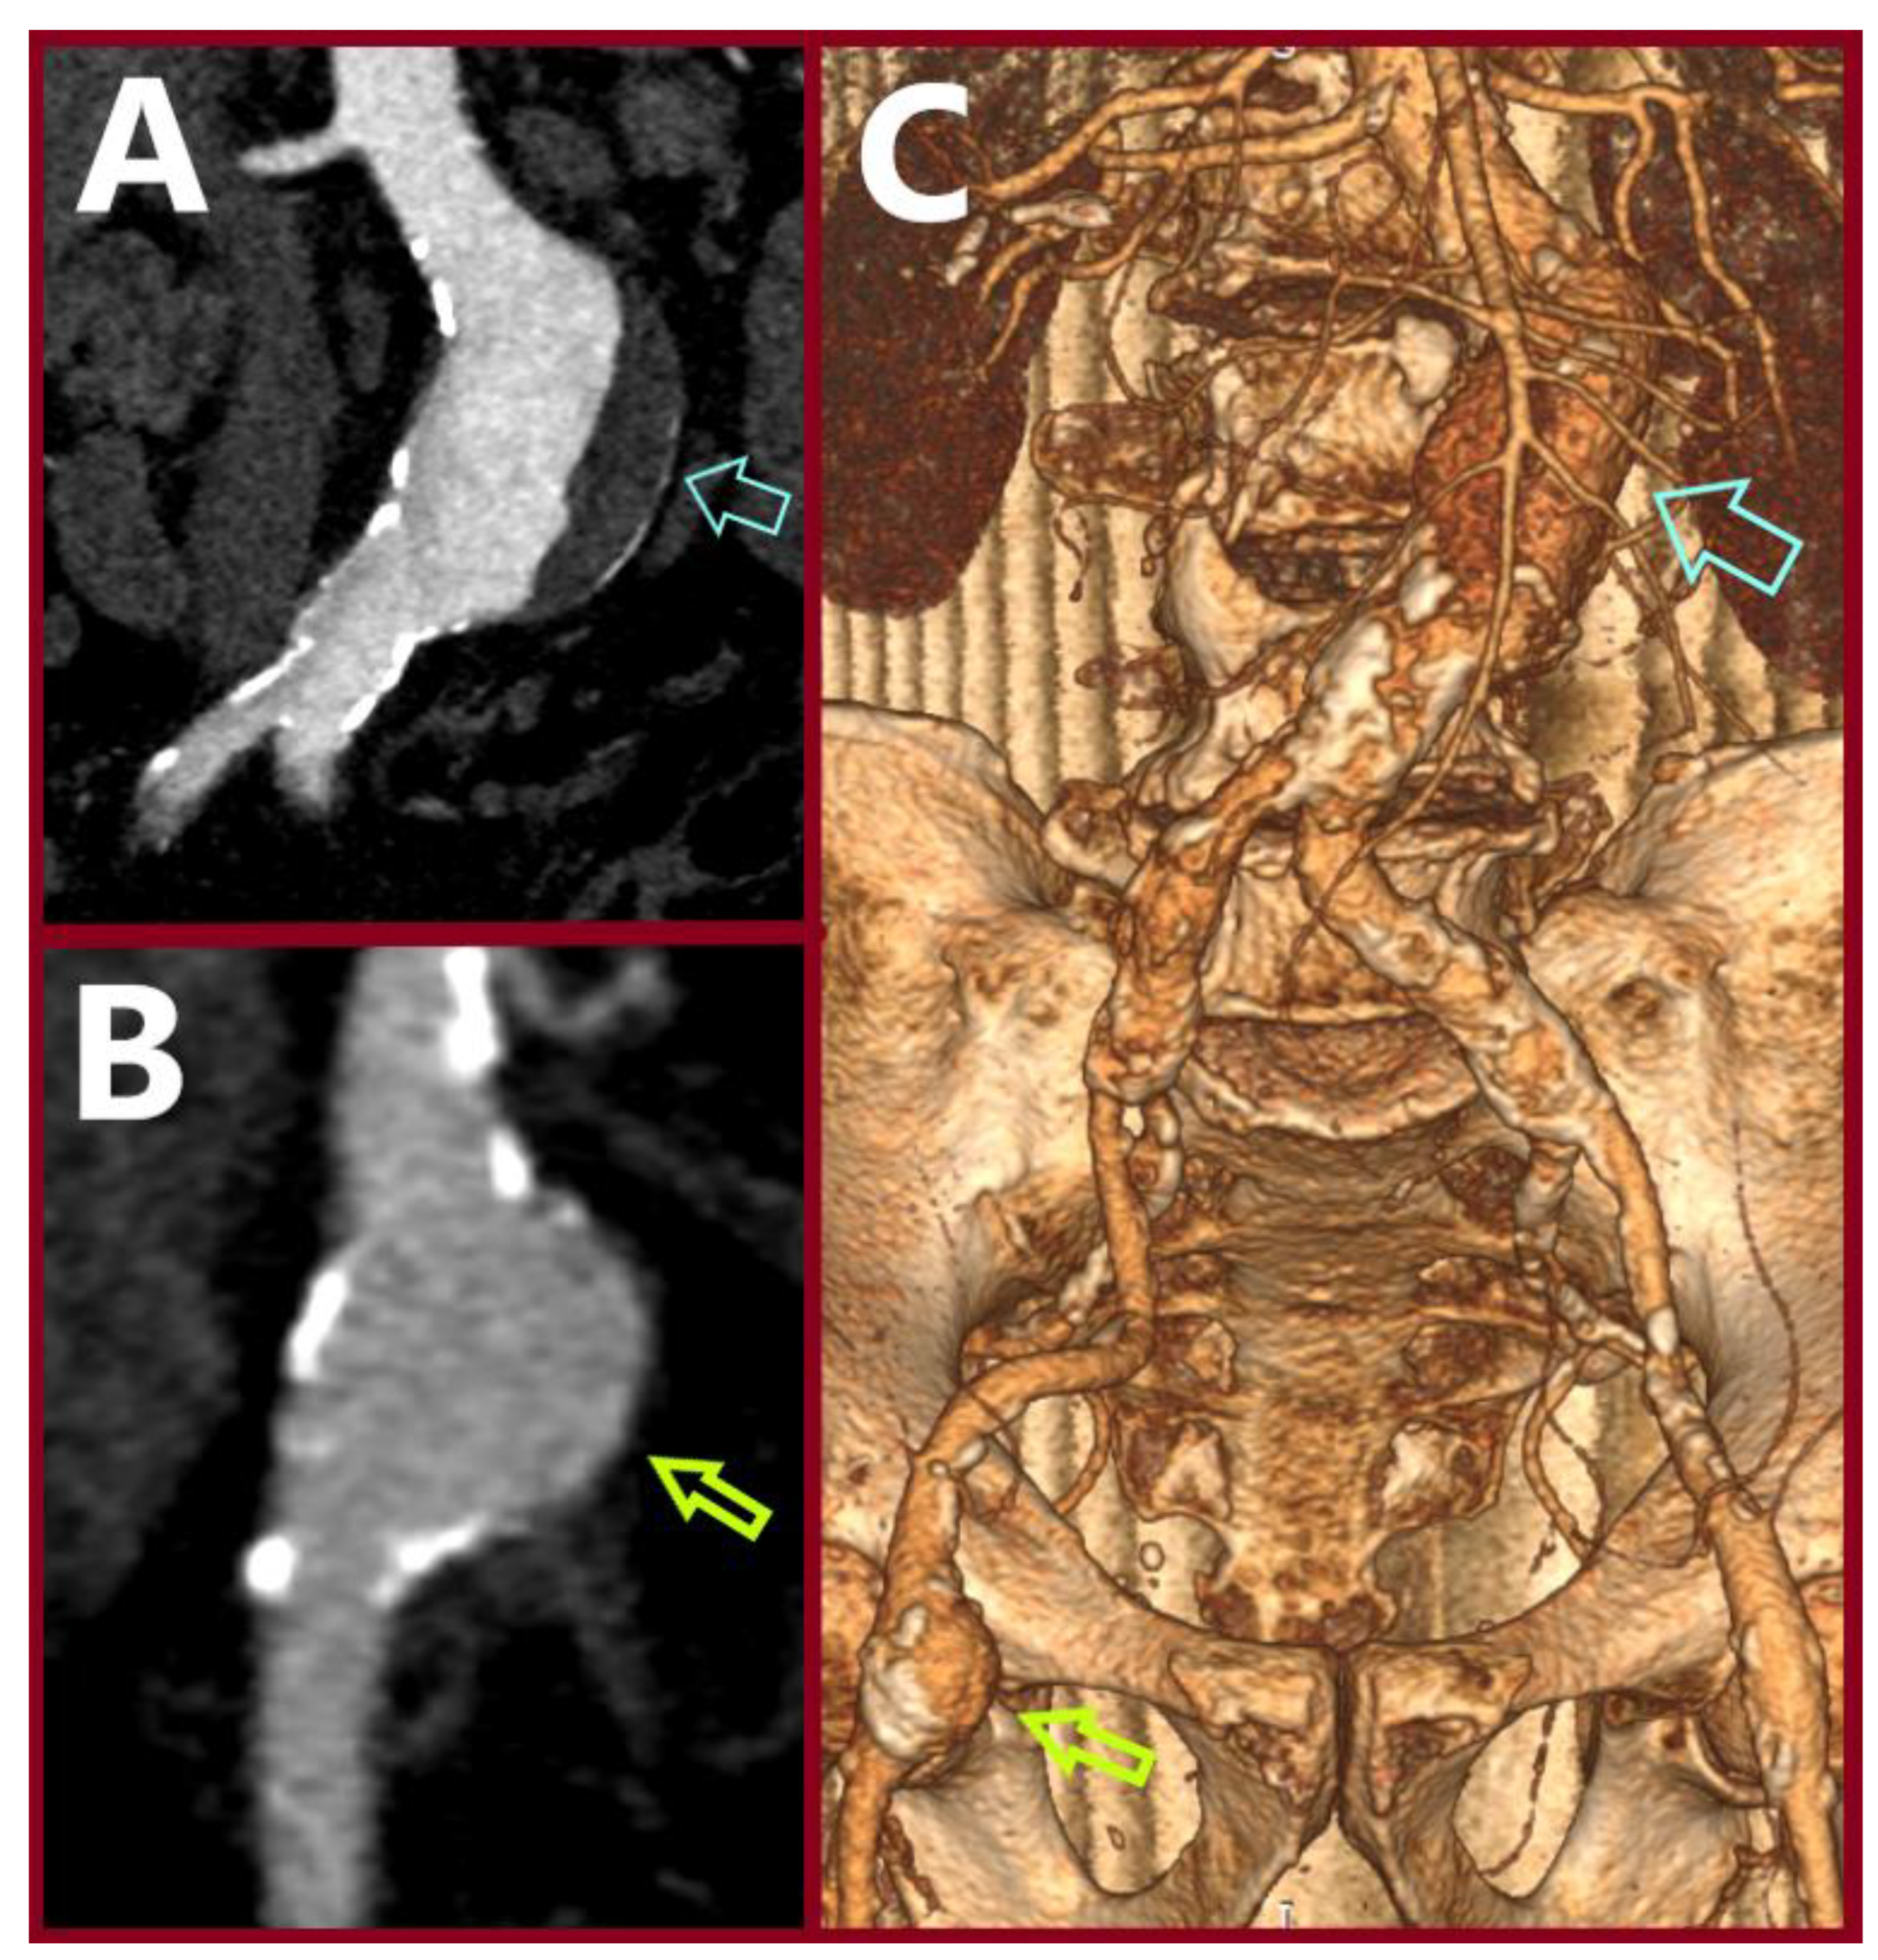

3.1. Case 1

3.2. Case 2

3.3. Case 3